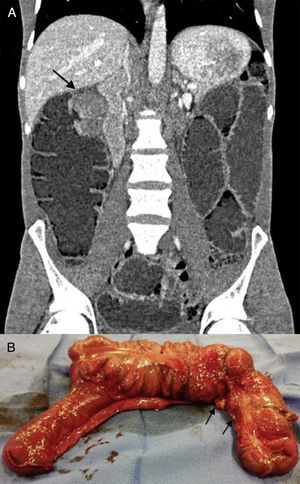

The second case was a 38-year-old man with no family history of colon cancer. He was recently diagnosed as seropositive for human immunodeficiency virus, stage A1, with a viral load of 120000 copies/ml. He presented with asthenia and 10-day progression of abdominal pain, nausea, vomiting, absence of bowel transit, and great abdominal distension. Plain x-ray showed marked small bowel dilation. Emergency CT scan identified an irregular 6 x 6cm mass at the level of the hepatic angle (fig. 2A) with proximal cecal dilation up to 6.2cm, along with multiple retroperitoneal lymph node conglomerates and millimetric hypodense lesions in the liver parenchyma. Emergency right hemicolectomy was performed, with the intraoperative finding of diffuse intestinal carcinomatosis (fig. 2B), mesenteric implants, and numerous hepatic lesions suggestive of metastasis.

The anatomopathologic diagnosis was poorly differentiated adenocarcinoma of the colon with > 50% signet ring cells, multiple metastatic peritoneal implants, lymph node conglomerates, and stage T4aN2bM1b. Immunohistochemistry showed microsatellite instability in the PMS-2 and MLH-1 genes and mutated K-ras gene.

The oncologic extension study revealed mediastinal adenopathies infiltrated with signet ring cell adenocarcinoma. Palliative chemotherapy was decided upon.